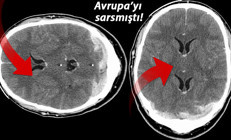

Oxford/AstraZeneca aşısı pandemi süresince eleştirilerin ve tartışmaların hep odağında oldu. Aşının Birleşik Krallık'ta kullanıma sunulması sonrası çok nadir görülen kan pıhtılarına bağlantı ölümler ilaçla ilgili güvenilirlik tartışmalarına yol açtı.